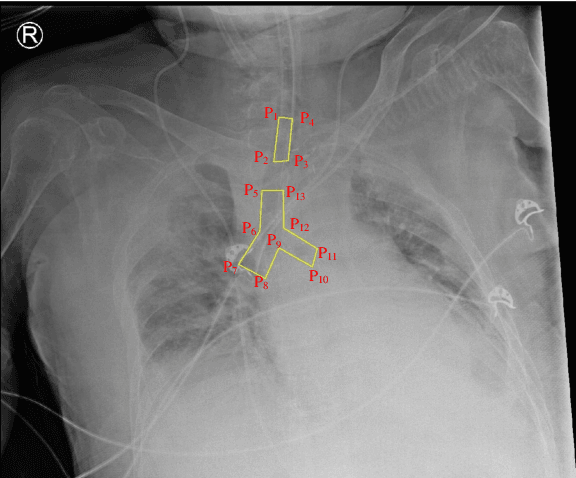

The image quality of portable supine chest radiographs is inherently poor due to low contrast and high noise. The endotracheal intubation detection requires the locations of the endotracheal tube (ETT) tip and carina. The goal is to find the distance between the ETT tip and the carina in chest radiography. To overcome such a problem, we propose a feature extraction method with Mask R-CNN. The Mask R-CNN predicts a tube and a tracheal bifurcation in an image. Then, the feature extraction method is used to find the feature point of the ETT tip and that of the carina. Therefore, the ETT-carina distance can be obtained. In our experiments, our results can exceed 96\% in terms of recall and precision. Moreover, the object error is less than $4.7751\pm 5.3420$ mm, and the ETT-carina distance errors are less than $5.5432\pm 6.3100$ mm. The external validation shows that the proposed method is a high-robustness system. According to the Pearson correlation coefficient, we have a strong correlation between the board-certified intensivists and our result in terms of ETT-carina distance.